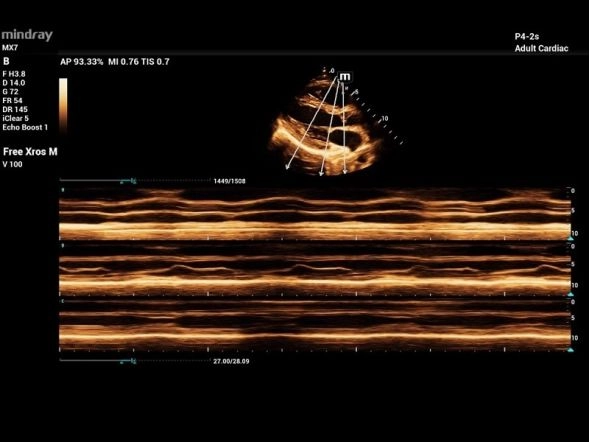

Исследование сердца взрослого анатомический M-режим

Исследование сердца взрослого TDI

Сердечный цикл